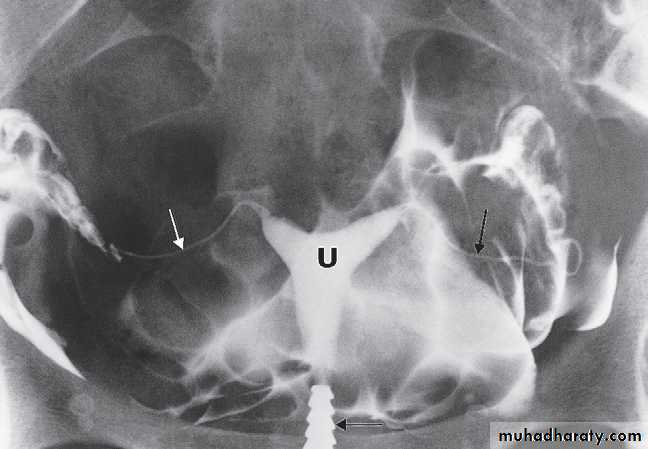

Detection of intrauterine contraceptive devices

The lost intrauterine contraceptive device (IUCD) is a relatively common problem and ultrasound should be the first investigation. Different devices have characteristic appearances. They are seen as highly reflective structures and their relationship to the uterine cavity can be determined.Hysterosalpingography is a contast study of uterus & both fallopian tube used to investigate selected cases ofinfertility in order to assess the patency of the fallopian tubes. A catheter with a seal to prevent leakage from the external cervical os is inserted into the uterus. Sufficient iodinated contrast is then injected under fluoroscopic control to fill the uterus and fallopian tubes .

If the fallopian tubes are patent, there is free spill into the peritoneum, recognized by the demonstration of contrast between loops of bowel. Congenital variations in uterine morphology, which may prevent maintenance of pregnancy, can also be assessed.